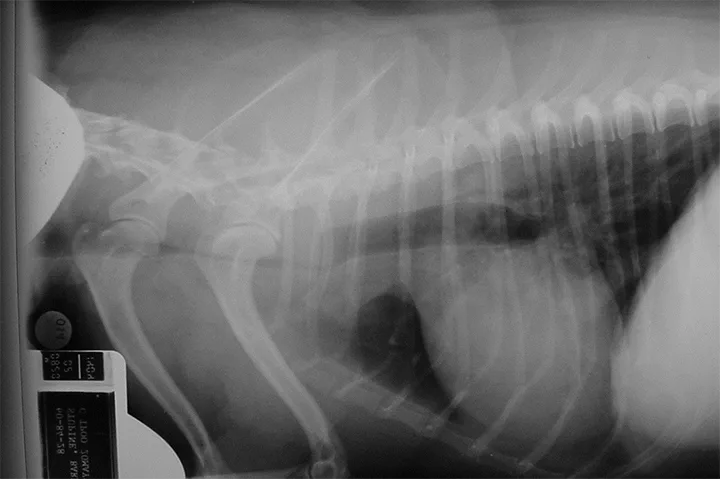

Thoracic Radiography

Thoracic radiography is warranted in all patients presented for cough. Particular attention should be placed on evaluation of the trachea and mainstem bronchi, as well as for signs of concurrent disease (eg, pulmonary, cardiac [Figure 1]). Cervical radiographs may be helpful for evaluation of the cervical trachea and thoracic inlet. However, radiographs only provide a snapshot in time; therefore, they may appear relatively normal even in a dog with significant tracheal collapse, depending on the respiratory phase captured on the images. In the author’s experience, the extent of tracheal disease is not truly represented on radiographs, and other imaging modalities may provide a more accurate clinical representation.

Lateral radiograph of a patient with severe focal collapse of the trachea in the thoracic inlet